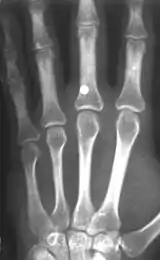

A BB with a velocity of 45 m/s (150 ft/s) has skin-piercing capability, and a velocity reaching 60 m/s (200 ft/s) can fracture bone.[5] The potential exists for killing someone; this potential increases with velocity, but also rapidly decreases with distance. The effective penetrating range of a BB gun with a muzzle velocity of 120 to 180 m/s (390 to 590 ft/s) is approximately 18 m (60 ft). A person wearing jeans at this distance would not sustain serious injury. However, even at this distance a BB still might penetrate bare skin, and even if not, could leave a severe and painful bruise. The maximum range of a BB gun in the 120 to 180 m/s (390 to 590 ft/s) range is 220 to 330 m (240 to 360 yd), provided the muzzle is elevated to the optimum angle.

- C. L. Tsui, K. L. Tsui, Y. H. Tang (2010). Ball bearing (BB) gun injuries